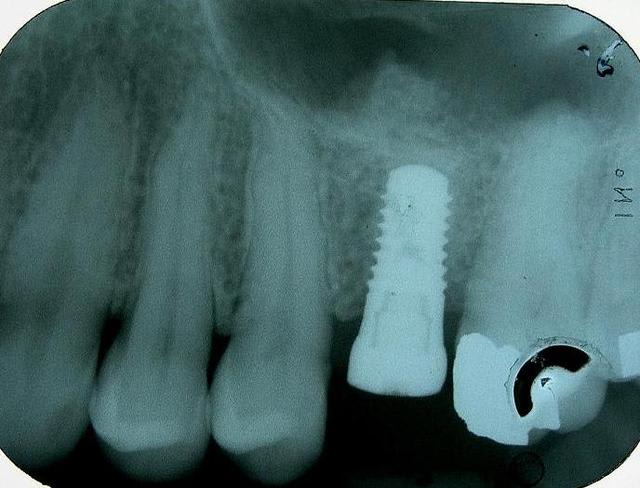

Patiente porteuse d'un bridge de + 10 ans réalisé par un confrère. Celui-ci ayant quitté la région, je la suis depuis peu.

J'ai dût extraire 26 (carie+++ sous une couronne unitaire)

Implant et vis de cica dans la foulée (couple >à 50N obtenue sous forant) (Nobel Replace Speedy WP 5*10mm)

Question: pourquoi à l'OPT l'implant parait toujours plus mésial ?

je remarque que ton implant est entièrement dans de l'os natif.

alors pourquoi la greffe, ou pourquoi pas un implant plus long?